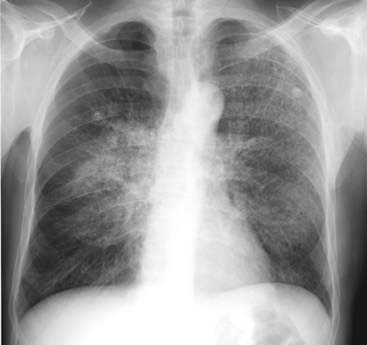

image

Figure 7-5 Pneumocystis carinii (jiroveci) pneumonia (PCP).

Diffuse interstitial lung disease is seen, which is primarily reticular in nature. Without the additional history that this patient had acquired immunodeficiency syndrome (AIDS), this could be mistaken for pulmonary interstitial edema or a chronic, fibrotic process such as sarcoidosis. No pleural effusions are present, as might be expected with pulmonary interstitial edema, and there is no evidence of hilar adenopathy, as might occur in sarcoid.